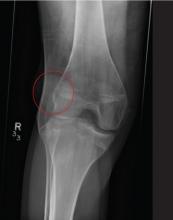

A 20-year-old man presents following a motor vehicle collision in which the car he was driving was broadsided by another vehicle. His air bag deployed, and the patient is now complaining of right-sided chest wall pain and right knee pain. His medical history is unremarkable. In a primary survey, the patient appears stable, with normal vital signs. Inspection of his right knee shows some deformity of the joint, with mild swelling and moderate tenderness. The patient is unable to perform flexion with his right knee. Good distal pulses are present, and sensation is intact. Radiograph of the right knee is obtained. What is your impression?

The radiograph demonstrates lateral dislocation of the patella, with no evidence of an acute fracture of any surrounding bones. The patella was easily reduced in the emergency department, and the patient was placed in a knee immobilizer. Orthopedic consultation was obtained.